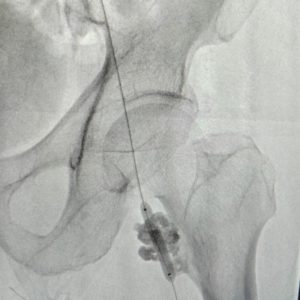

2. Sclerotherapy for Vascular Malformations (Head to Toe)

• The Problem: Birthmarks or abnormal tangles of blood vessels (like hemangiomas or venous malformations) that can be painful, disfiguring, or prone to bleeding.

• Our Solution: We use ultrasound guidance to inject a sclerosing agent directly into the malformation. This medicine irritates the vessel lining, causing it to collapse and shrink over time.

• Patient Benefit: A highly targeted treatment to improve appearance, reduce pain, and prevent complications without affecting surrounding skin or tissues.